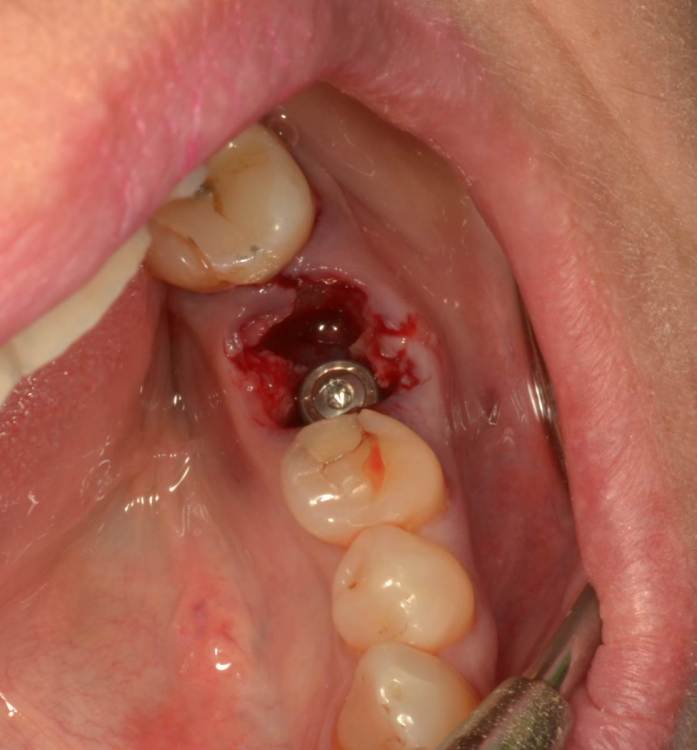

Большой Зеленый Опубликовано 27 мая, 2022 Поделиться Опубликовано 27 мая, 2022 Аналогично..) 4 1 Ссылка на комментарий

Большой Зеленый Опубликовано 27 мая, 2022 Поделиться Опубликовано 27 мая, 2022 Через 9 лет. Есть немного рецессии.. 2 Ссылка на комментарий